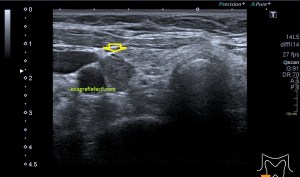

En la imagen 3 ves una imagen de un lipoma, mide 7 cms, la huella de la sonda mide 5cms, la «panoramic view» posee una regla centimetrada que sigue el contorno de la imagen, justo en la profundidad de la misma y lo marca la flecha amarilla. La profundidad la marca la flecha roja y la flecha blanca marca el rango centimetral de los 5cms, fíjate que la línea blanca es ligeramente mayor cada 5 cms. Sirve de referencia, como en la imagen 4 donde ves una colección en el glúteo de más de 10 cms.